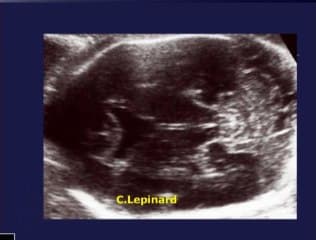

La médiathèque du Collège Français d'Échographie Fœtale (CFEF) constitue l'une des plus importantes collections de ressources vidéo dédiées à l'échographie fœtale en France. Avec plus de 3 261 vidéos, elle couvre l'ensemble des thématiques liées à la pratique échographique prénatale.

Vous y trouverez des conférences présentées lors des congrès nationaux et internationaux, des cours magistraux dispensés par des experts reconnus, des démonstrations pratiques sur des cas cliniques réels, ainsi que des podcasts et tables rondes sur les dernières avancées de la spécialité.